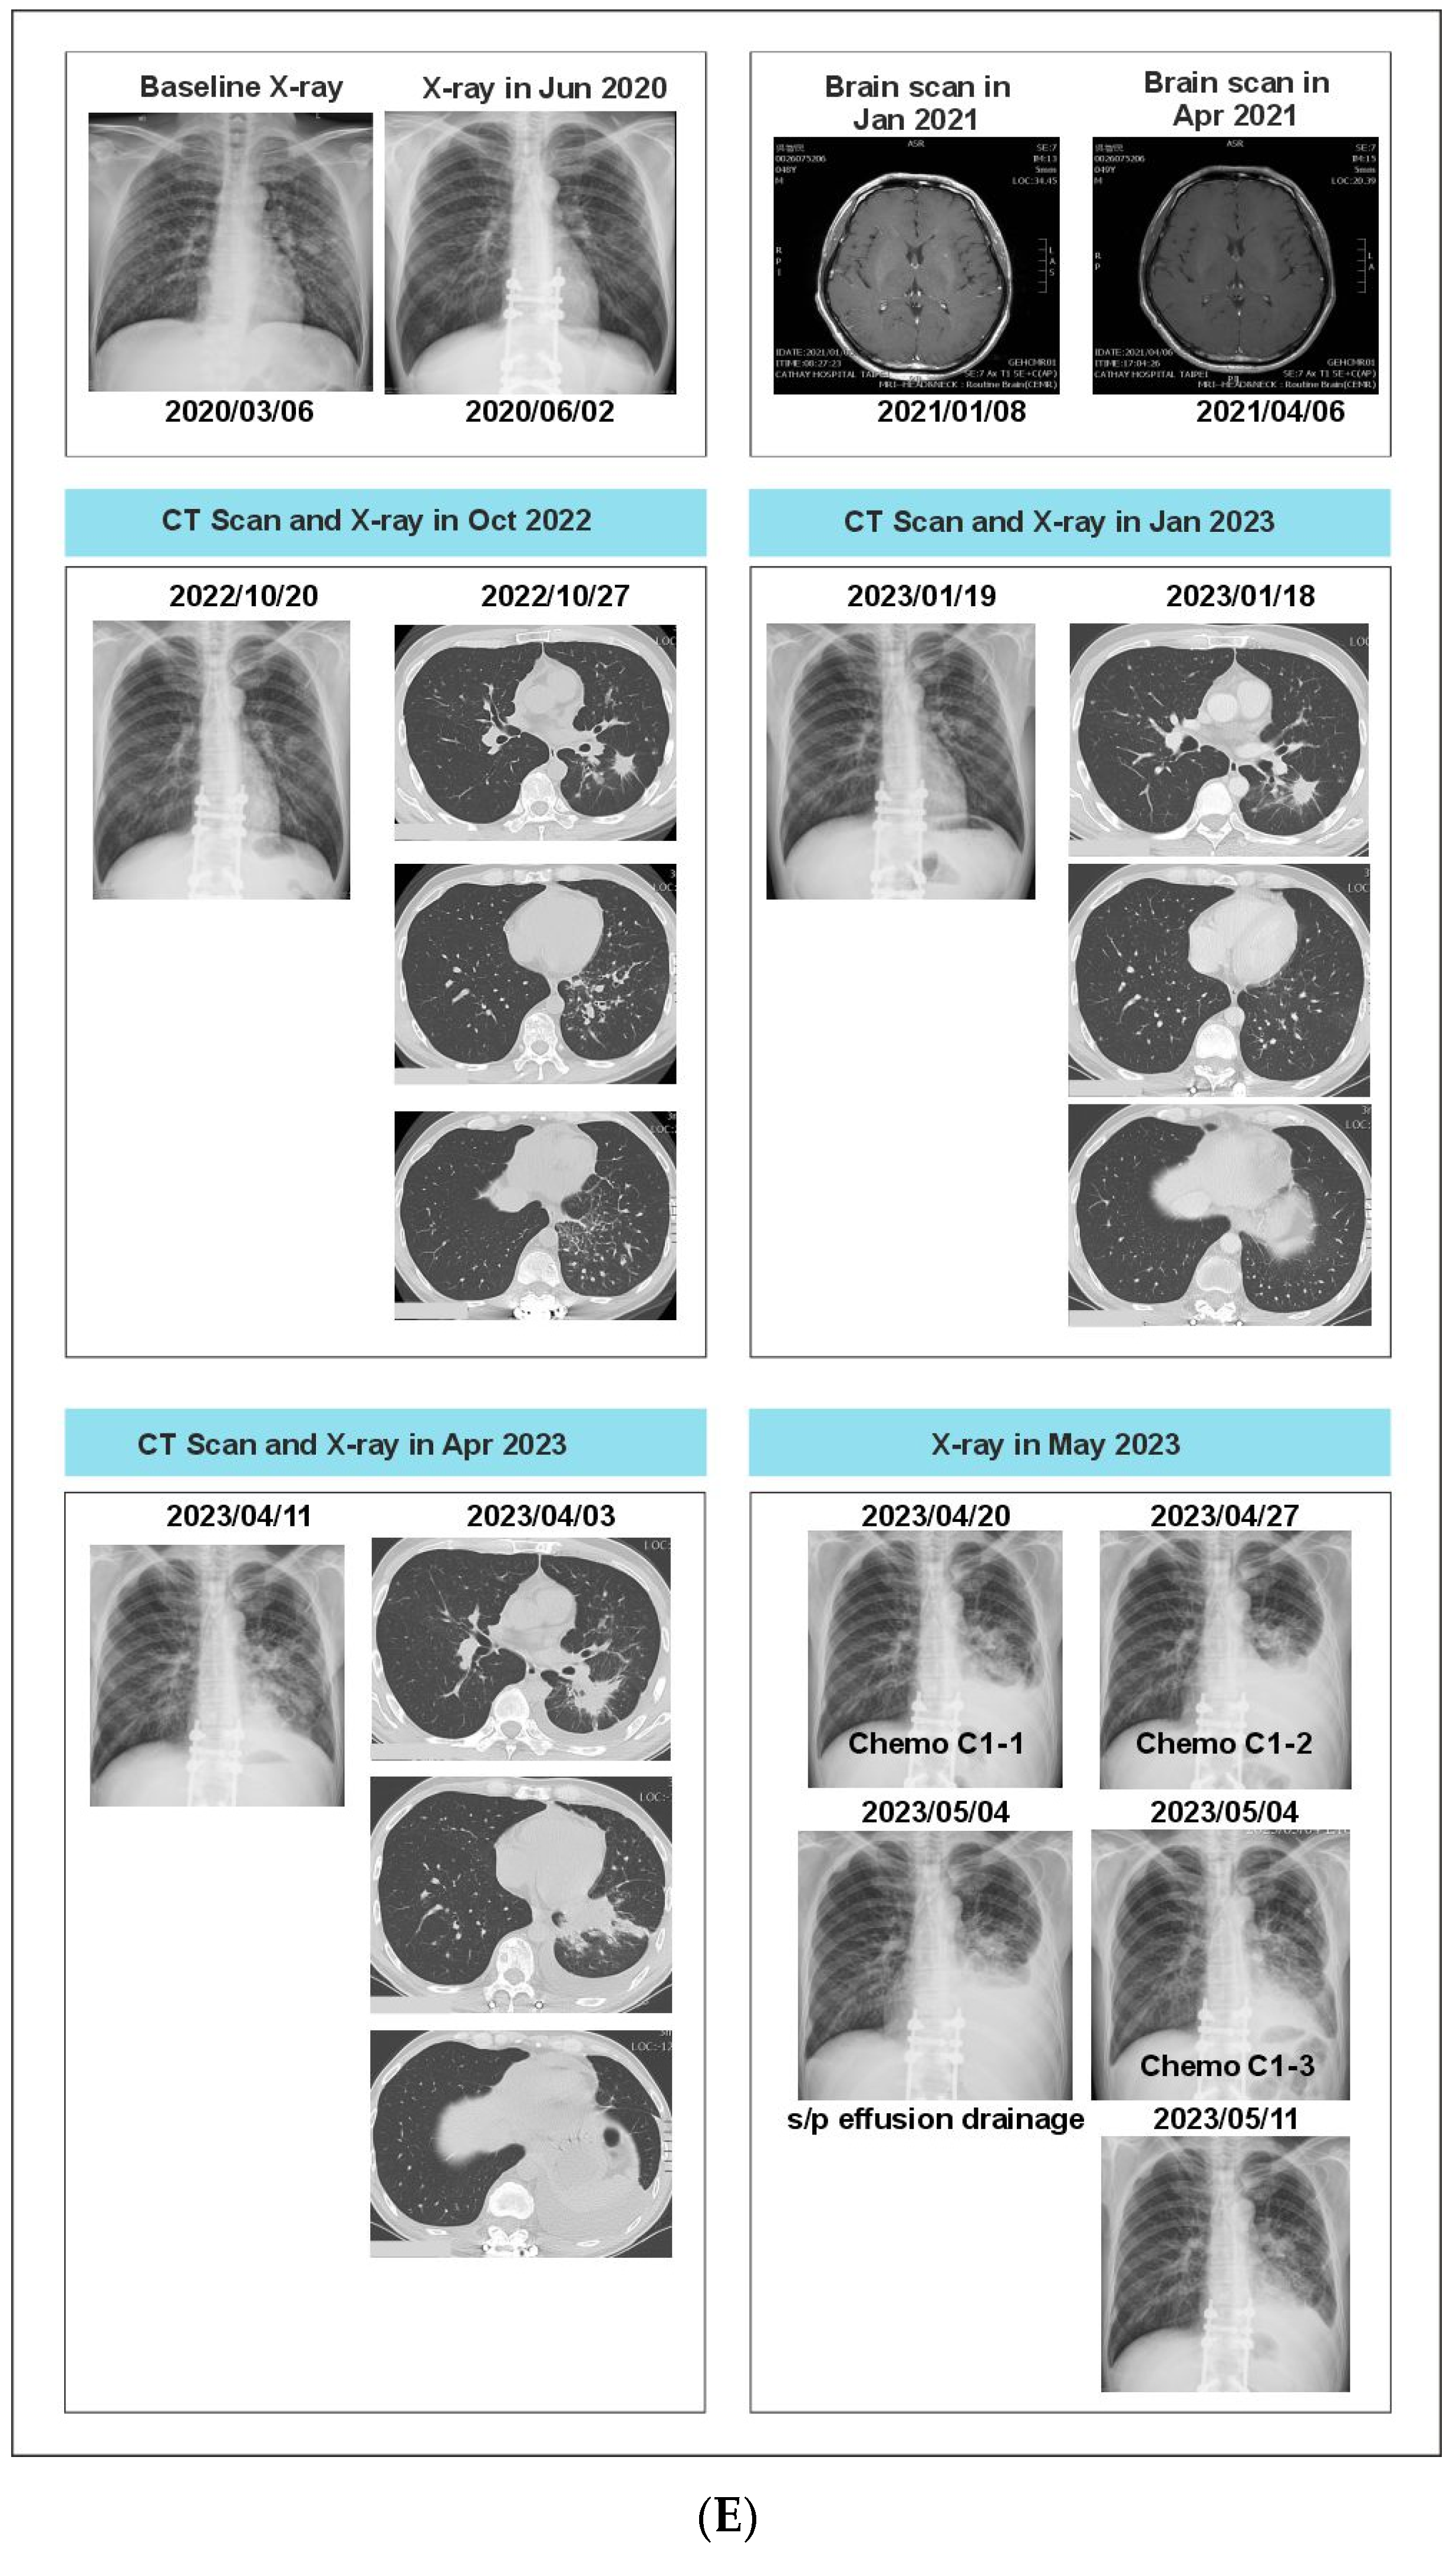

2.6. Case 6: Serial Monitoring Detects Actionable Molecular Profiles throughout the Disease